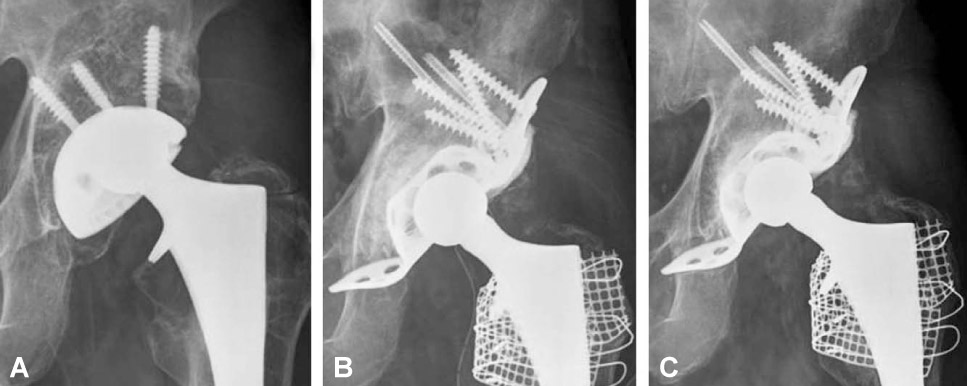

Thirty-six acetabular revisions were performed in 36 patients with use of the reinforcement ring and structural or morselized allograft, between 1997 and 2005, in thirty-six patients. According to the AAOS classification, thirty-four cases of acetabular defects were Ttype III, and two were Ttype IV. Mean follow-up period after surgery was 7.2 years.

The mean Harris hip score was 92.3, which was significantly increased compared with the preoperative score. (p<0.001). There were five failures: a case of aseptic loosening of Muller ring, two cases of infection (5.4%) and two cases of hip dislocation (5.4%). Graft incorporation and bone remodeling occurred successfully in all hips, but in the case of aseptic loosening in which the ring fixation had been inadequate at the time of surgery. The success rate was 91.7% with a mean follow-up of 7.2 years, if the cases of revision or loosening of the component were classified into failure cases.

Patients treated with acetabular revision with three kinds of reinforcement ring had reconstitution of periacetabular bone stock as well as good clinical and radiographic results. For the good results, the secure implant fixation during the surgery should be confirmed and we should completely understand the characters of the each kinds of reinforcement rings.